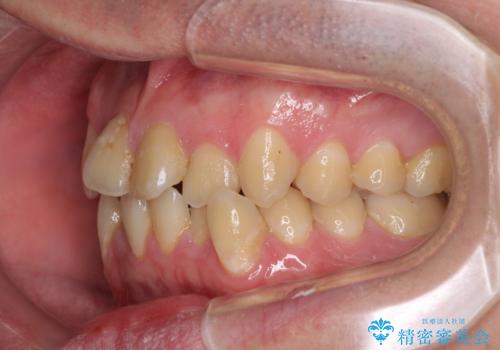

- 上下のデコボコと前歯のクロスバイトを改善したいとのことで来院された患者様です。

マウスピース矯正での自己管理には自信がないとのことで、ワイヤー装置による矯正治療を行うこととしました。

デコボコの程度は強かったのですが、口元の突出感はなかったため、非抜歯矯正としました。